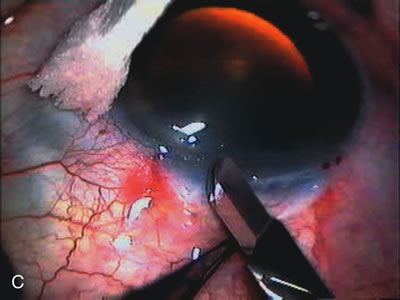

Nonpenetrating procedures as they exist today generally decrease postoperative complications but do not reduce IOP as successfully as trabeculectomy.140 The success rate also appears to be highly dependent on race, length of topical antiglaucoma therapy, and prior ocular surgery.141,142 Deep sclerectomy combined with phacoemulsification results in an IOP reduction similar to phacotrabeculectomy at one year with comparable visual outcome.143 Phacoviscocanalostomy lowers IOP by approximately 33%144 through either a one- or two-site approach145 (Fig. 4). Nonpenetrating procedures are in evolution, and their place in long-term glaucoma care is still unclear.

Fig. 4. Viscocanalostomy with deep sclerectomy and phacoemulsification. Nonpenetrating filtration procedures (NPFS) may be combined with phacoemulsification. Patients with mild disc damage and a history of limited topical drug therapy are the best candidates. Patients who require an IOP in the low teens are not good candidates for NPFS. By definition, NPFS is designed to lower IOP without penetrating into the anterior chamber, thereby avoiding the complications associated with trabeculectomy. Viscocanalostomy is intended to allow aqueous to percolate through a trabeculodescemetic membrane into a subscleral cavern created by the deep sclerectomy. The aqueous diffuses from the cavern into the dilated ostia of Schlemm's canal and into the episcleral venous plexus. A. Fashion a uniform 300-micron superficial scleral flap 1 mm into clear cornea. B. Construct a second 600-micron deep flap that facilitates the unroofing of Schlemm's canal, seen as the darker area. C. Use viscoelastic to dilate the ostia of Schlemm's canal. The major problem with viscocanalostomy is the eventual closure of the ostium decreasing flow to the episcleral plexus. D. Dissect the deep flap anteriorly into clear cornea creating the trabeculodescemetic membrane. This membrane is clearly seen between the scleral spur and the bend of the deep flap. The integrity of this membrane ensures the nonpenetrating portion of the surgery. Another problem with NPFS is the eventual fibrosis of this initially transparent membrane requiring goniopuncture. E. Deep sclerectomy gets its name from removal of the deep flap. Removal of this flap creates the potential subscleral space for accumulation of aqueous before it enters Schlemm's canal and exits the episcleral venous plexus. After removal of the deep flap, the superficial flap is sutured into place and conjunctiva closed. Approximately half of these procedures develop a shallow bleb.